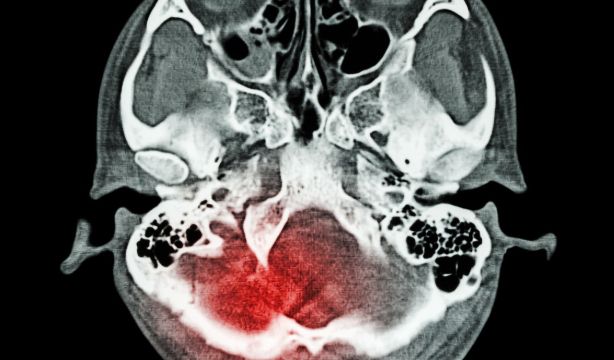

Y una asociación diferente de los factores de riesgo con la gravedad del evento puede medirse a través de la diferencia entre el ictus isquémico frente a la hemorragia intracerebral (HIC), ya que ésta se relaciona con la gravedad del evento, como se apunta en un estudio de 'Jama Network'.

De los pacientes con ACV, 4.848 tuvieron uno grave y 8.612 uno de leve a moderado. El ACV grave se definió como aquellos con resultados que iban desde la incapacidad de caminar o cuidarse por sí mismos sin ayuda, hasta la necesidad de cuidados de enfermería constantes o la muerte. El de leve a moderado incluyó a aquellos con resultados que iban desde la ausencia de síntomas hasta la necesidad de alguna ayuda con el cuidado personal, pero con capacidad de caminar sin apoyo de otros.